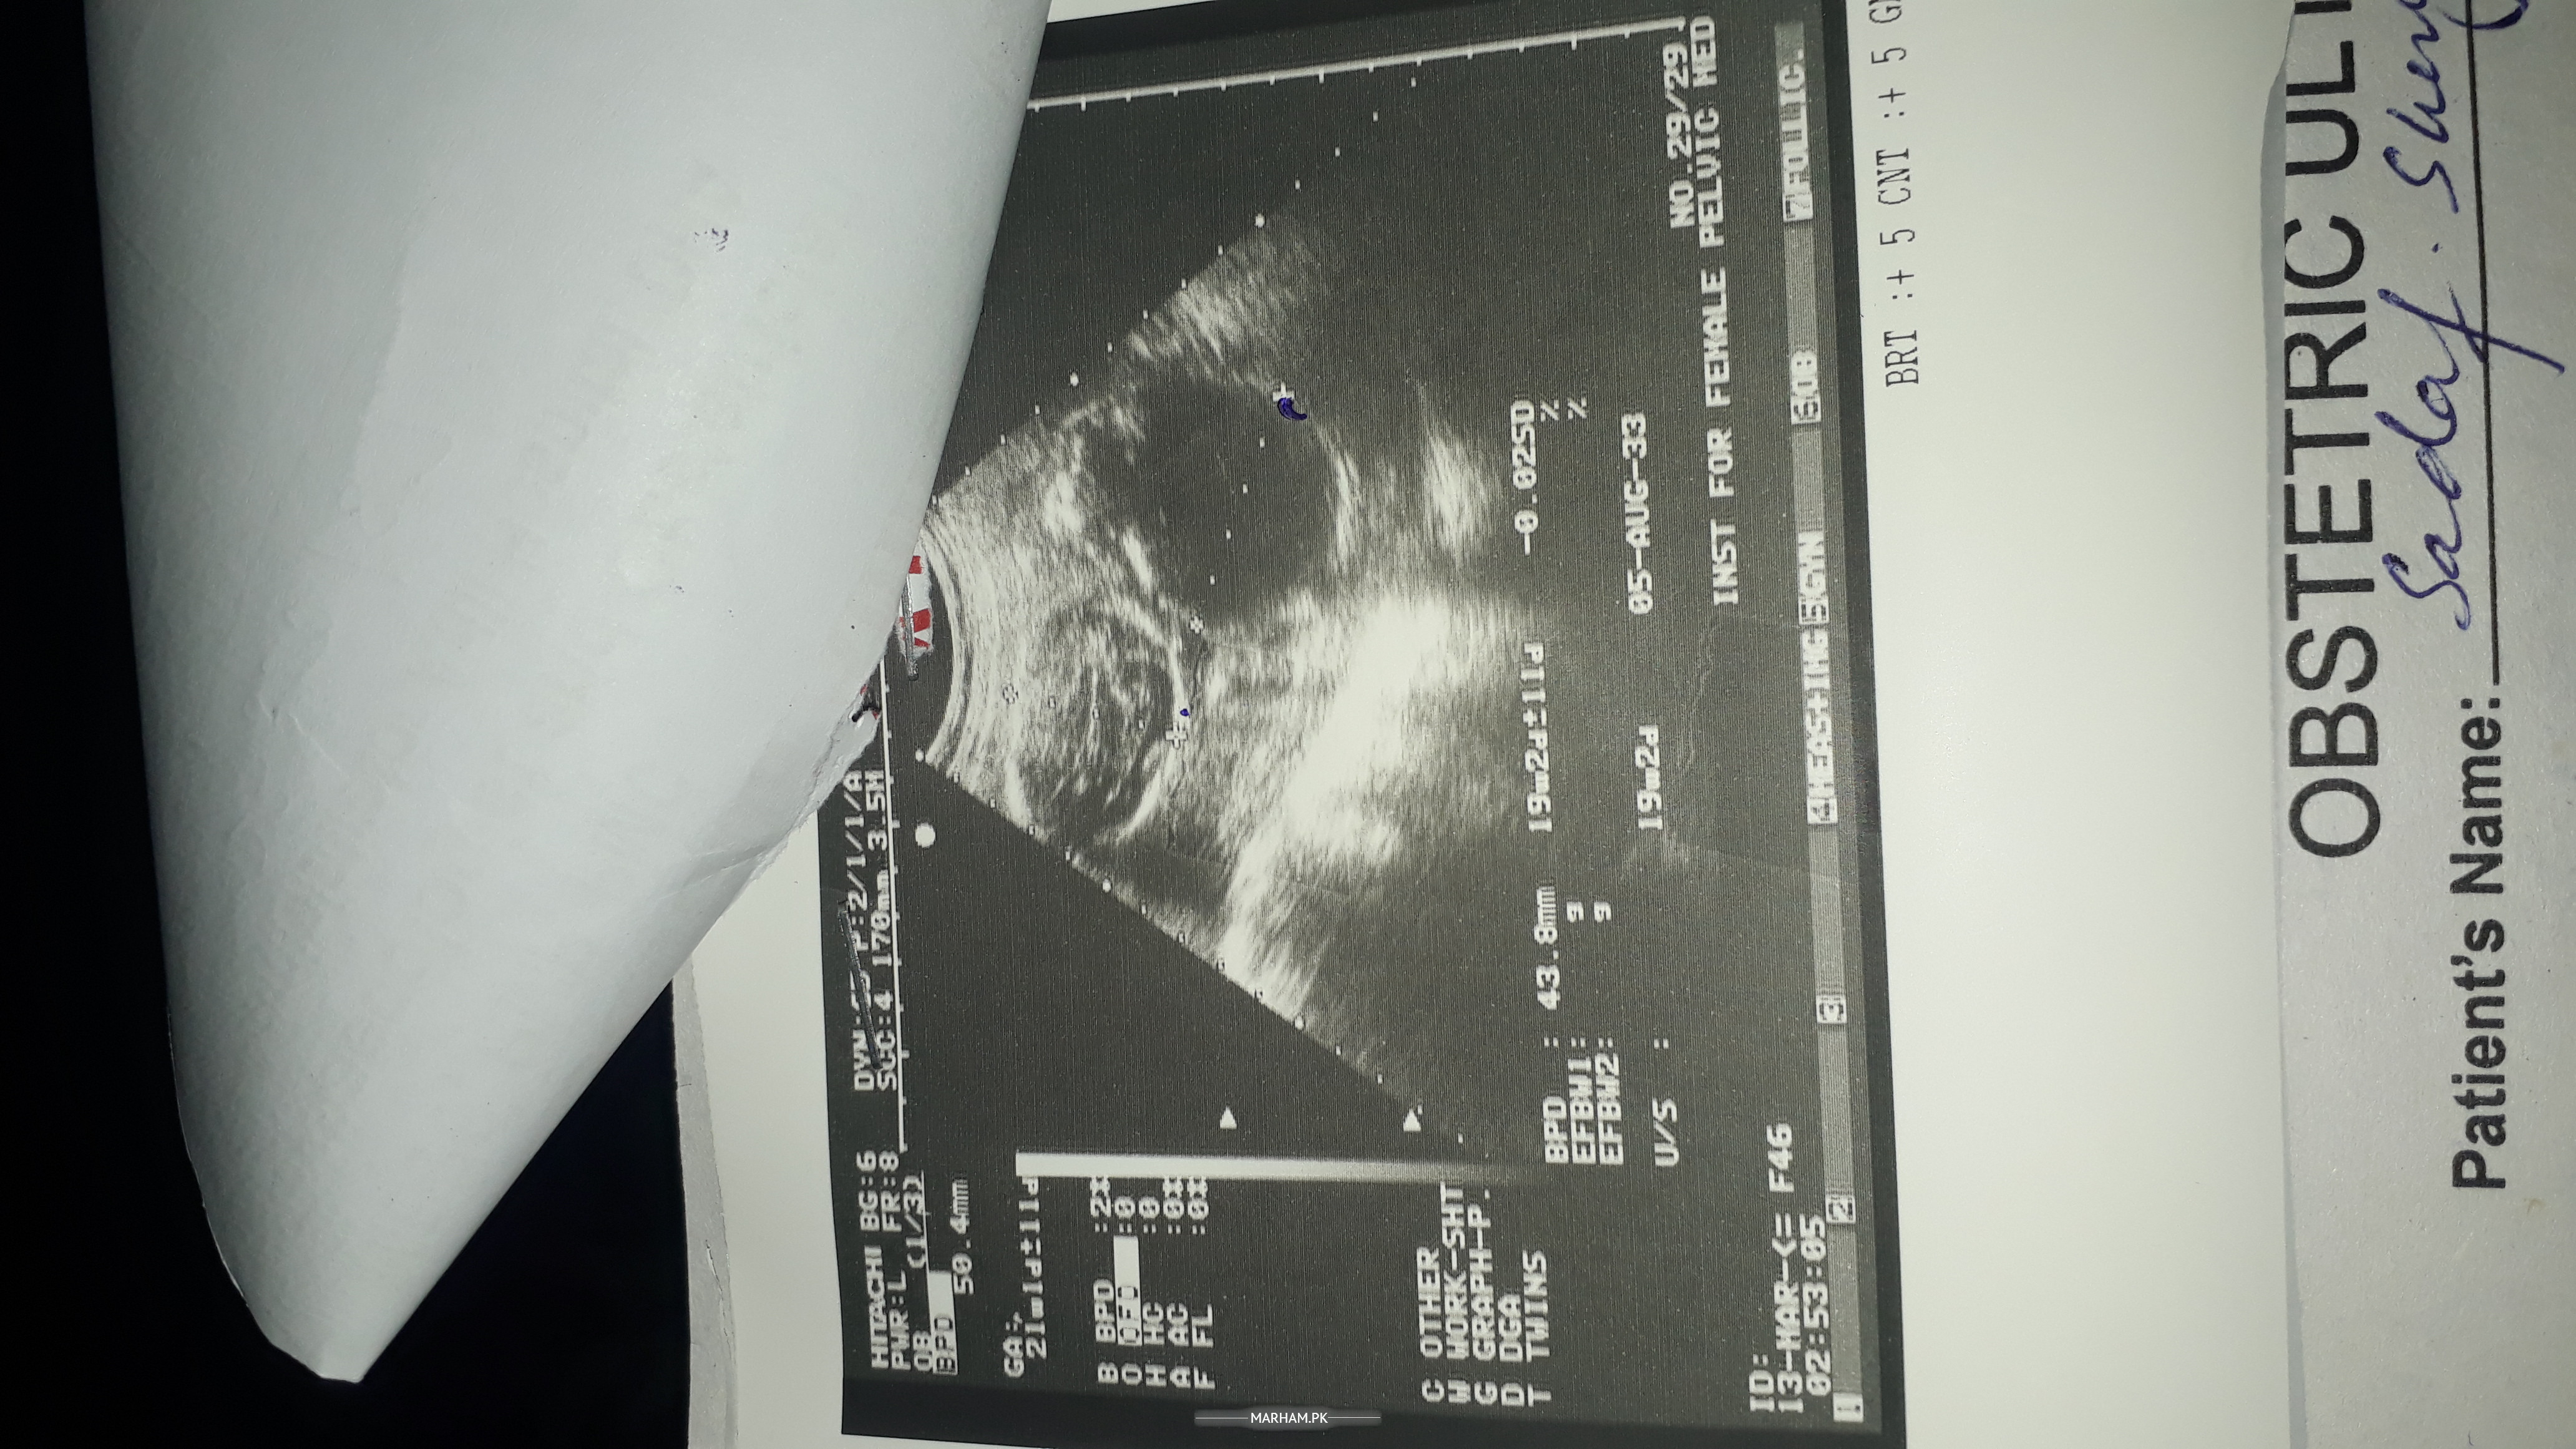

I already done my ultrasound mam

chk my ultrasound

kindly meri report chk kr k bta dein

my report

b ultrasound

report

Share your ultrasound report

kindly baby gender bi bta dein ultrasound dekh k